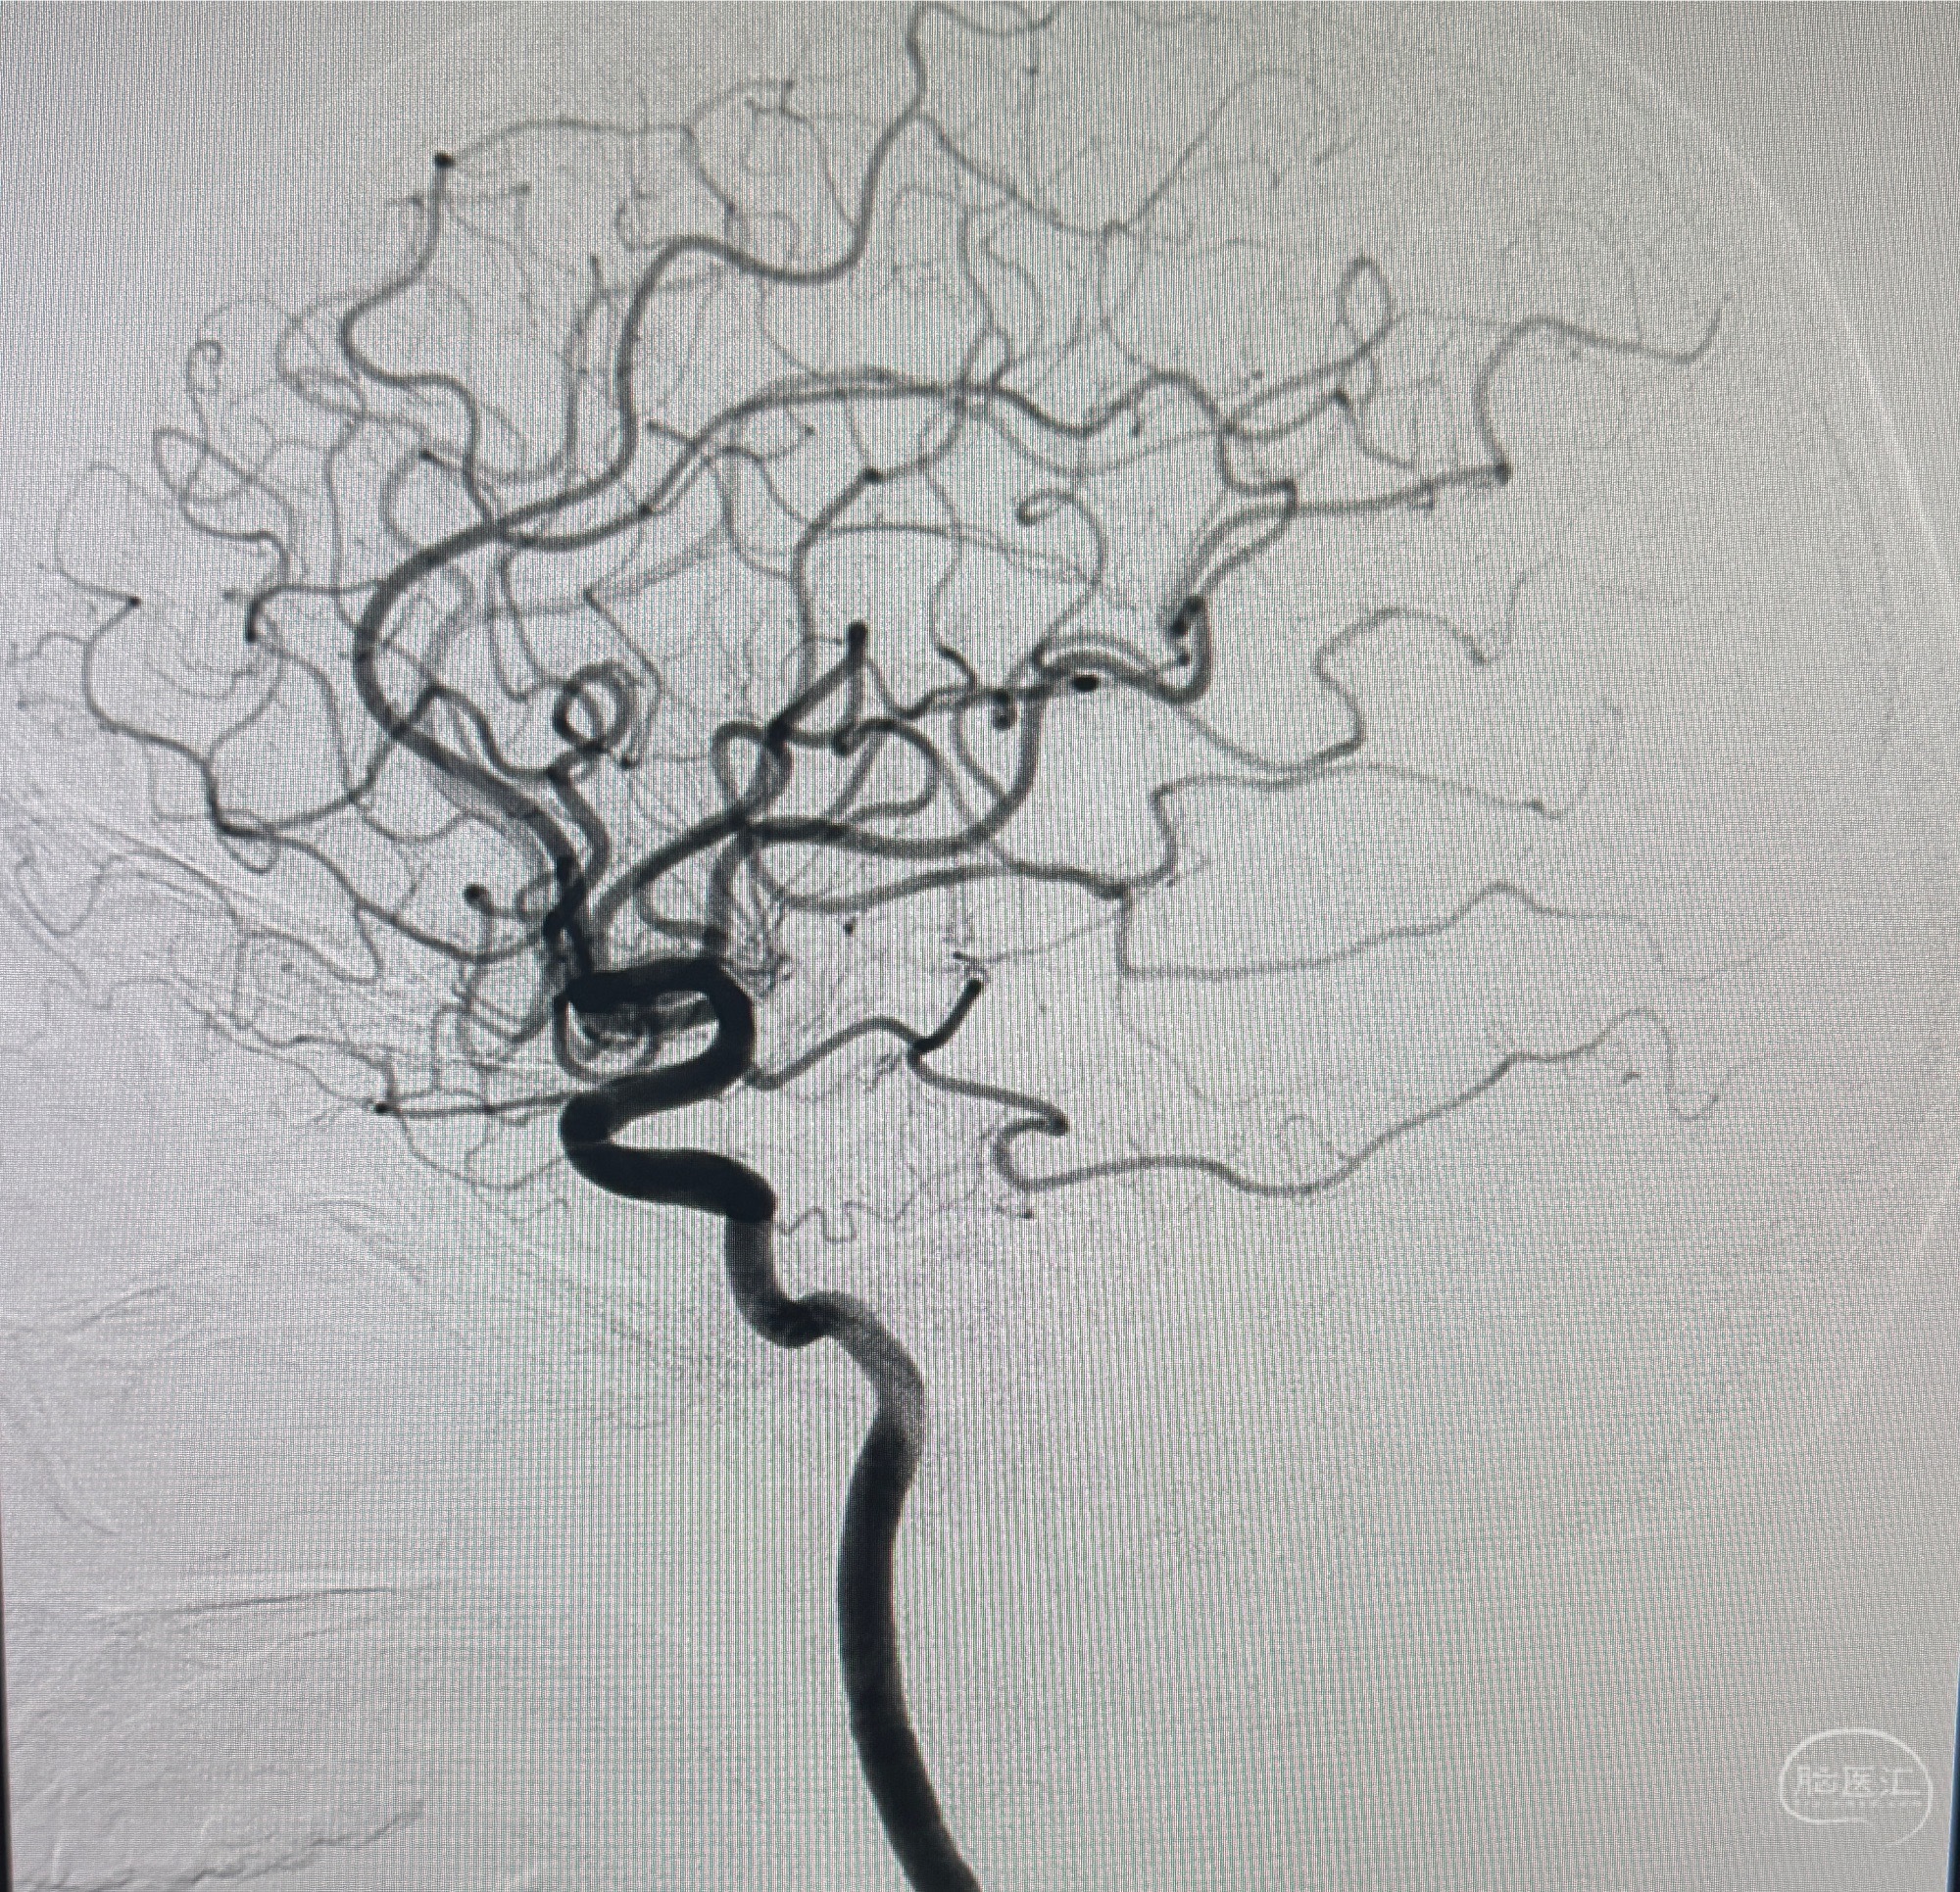

2023.07.12 江苏省泰州市人民医院在局麻下行脑血管造影提示左侧C5段动脉瘤(3.44*3.93mm)。

2023.07.24DSA+全麻下颅内动脉瘤密网支架+弹簧圈辅助干预